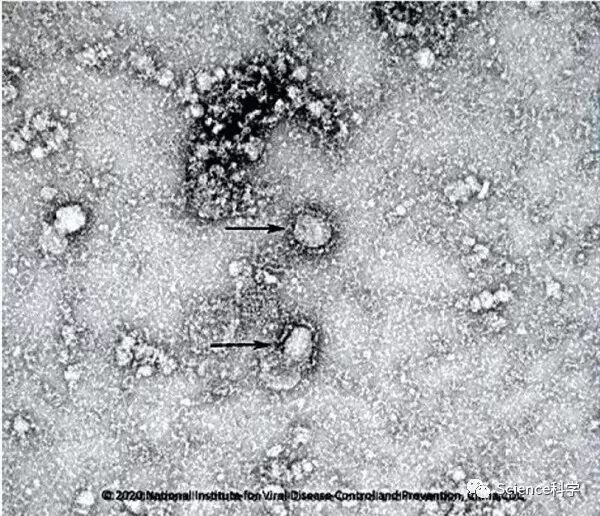

此外,中国疾病预防控制中心、国家微生物科学数据中心、国家病原微生物资源库近日联合发布了成功分离的第一株新型冠状病毒毒种信息,及其电镜照片、核酸检测引物、探针序列等信息,这是国内首次发布的相关重要权威信息。

目前为止,公布的毒种信息共有两个,一个是“新型冠状病毒武汉株01”,采自武汉临床患者,1月6日分离:

二个是“新型冠状病毒武汉株02”,采自武汉环境样本,分离时间1月22日: